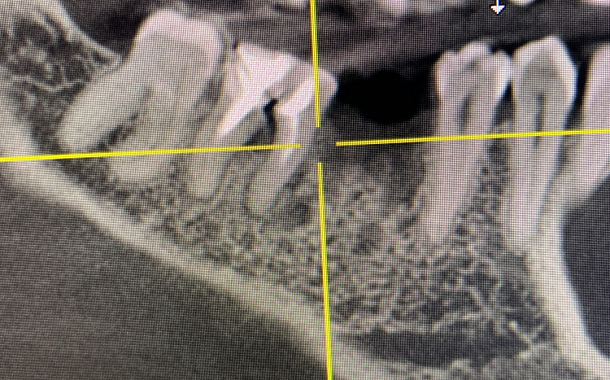

По 3D компьютерной томографии определяет возможность установки имплантата, немедленной фиксации временной коронки в день операции и объем пластических манипуляций. Совместно с врачом-стоматологом ортопедом планирует вид ортопедической конструкции и положение имплантата.

Компьютерная томография в формате 3D - важный диагностический инструмент стоматолога. На полученном объемном снимке стоматолог видит все нюансы вашей зубочелюстной системы: состояние костной ткани челюстей, зубов и височно-нижнечелюстного сустава. Именно томография позволяет доктору составить план и объем предстоящего оперативного вмешательства.